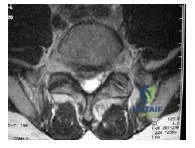

The axial computed tomography scan depicts a patient with spinal stenosis (Slide). The primary source of neural compression is impingement on the traversing nerve root by the:

Correct Answer: Superior facet of the level below

Explanation:

Spinal stenosis involves narrowing of the spinal canal by a combination of factors. Degeneration of the disk with dehydration allows loss of disk height and bulging posteriorly into the canal. The ligamentum flavum becomes redundant at the segment due to loss of the disk height and buckling of the ligament. C hief among the sources of compression, however, is the overgrowth of the facet joint, which acts to autostabilize the motion segment. The facets are oriented in an oblique plane, depending on the level involved. The superior facet of the subjacent vertebral body lies anterior and lateral to its counterpart from the level above, forming a shingle configuration. The superior articular process, therefore, lies adjacent to the shoulder of the traversing nerve root and is a significant source of lateral recess stenosis.